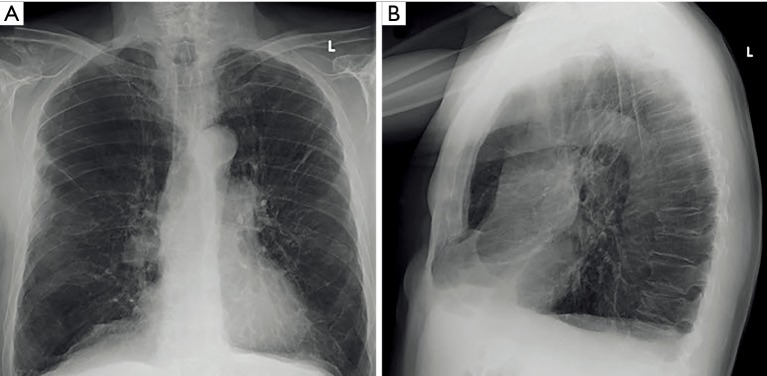

Findings in chest radiographs that should be evaluated in the initial evaluation of an LVR candidate are additional interstitial pulmonary disease other than emphysema, significant pleural scarring, and pulmonary nodules (Figure 1).

Figure 1.

Features of emphysema in conventional radiography. (A) Posteroanterior chest X-ray in a 72-year-old male patient with COPD GOLD III showing hyper-expanded lungs with upper lobe predominant emphysema; (B) lateral projection flattening of the diaphragmatic domes as well as increased anteroposterior diameter and increased retrosternal airspace can be noted. COPD, chronic obstructive pulmonary disease; GOLD, Global Initiative for Chronic Obstructive Lung Disease.

However, the value of posterior anterior (PA) and lateral chest radiograph is limitedly in LVR evaluation: chest radiography has only a sensitivity of 40% in detecting emphysema (26), and low specificity with high interobserver disagreement hamper a reliable and repeatable quantification of emphysema severity in COPD patients (27). Nevertheless, chest radiography as a fast, widely available, and easy to perform imaging modality at low cost and low radiation dose plays an important role in follow-up of COPD patients. Chest radiography is widely used for postoperative evaluation after LVR or after placement of endobronchial valve, sealant or coil implantation and its early or late complications such as pneumothorax or device displacement. Additionally, chest radiography is essential for pneumothorax management in endobronchial LVR.